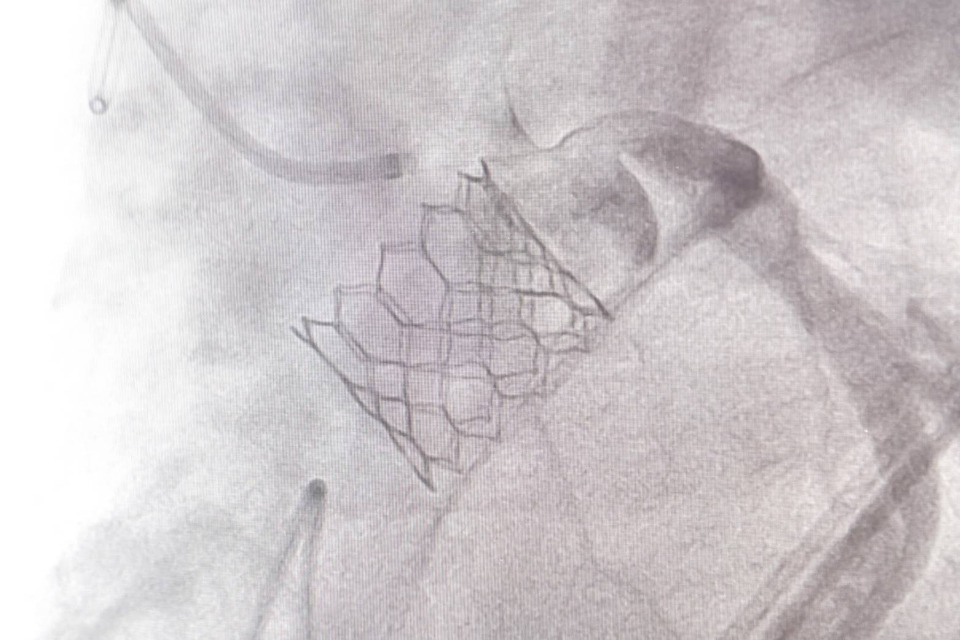

เมื่อเวลา 11.30 น.วันที่ 4 ธ.ค.2568 นพ.ดนณ แก้วเกษ อายุรแพทย์หัวใจและหลอดเลือด เปิดเผยว่า โรคลิ้นหัวใจเอออร์ติกตีบขั้นรุนแรงเป็นภาวะที่พบได้มากในผู้สูงอายุ และอาจนำไปสู่อาการเหนื่อยง่าย เจ็บหน้าอก เวียนศีรษะ หรือภาวะหัวใจล้มเหลวได้ การรักษาแบบดั้งเดิมคือการผ่าตัดเปิดหน้าอกเพื่อเปลี่ยนลิ้นหัวใจ แต่ผู้ป่วยบางรายมีความเสี่ยงสูง ไม่เหมาะกับการผ่าตัด ดังนั้นวิธีการรักษาแบบ TAVI (Transcatheter Aortic Valve Implantation) หรือการเปลี่ยนลิ้นหัวใจเอออร์ติกโดยไม่ต้องผ่าตัดเปิดหน้าอก จึงเข้ามามีบทบาทสำคัญ ซึ่งข้อดีของ TAVI คือไม่ต้องเปิดหน้าอก ไม่ต้องหยุดหัวใจ โดยแพทย์จะผ่าตัดใส่ลิ้นหัวใจเทียมผ่านทาง หลอดเลือดแดงที่ขาหนีบ ทำให้ผู้ป่วยฟื้นตัวเร็วมาก หลายรายกลับบ้านได้ภายใน 2–3 วัน

"ศูนย์หัวใจสิริกิติ์ฯ ใช้เทคโนโลยีลิ้นหัวใจรุ่นใหม่ที่พัฒนาให้วางตำแหน่งได้แม่นยำ ลดความเสี่ยงของภาวะแทรกซ้อน เช่น เลือดออก หลอดเลือดบาดเจ็บ หรือการนำไปสู่ภาวะการเต้นผิดจังหวะ ทีมแพทย์ Heart Team ซึ่งประกอบด้วยแพทย์โรคหัวใจ แพทย์หัตถการ แพทย์ศัลยกรรมหัวใจ วิสัญญีแพทย์ และทีมพยาบาลเฉพาะทาง จะร่วมกันวางแผนการรักษาและประเมินอย่างละเอียดในผู้ป่วยแต่ละราย เพื่อให้ได้ผลลัพธ์ที่ปลอดภัยที่สุด"